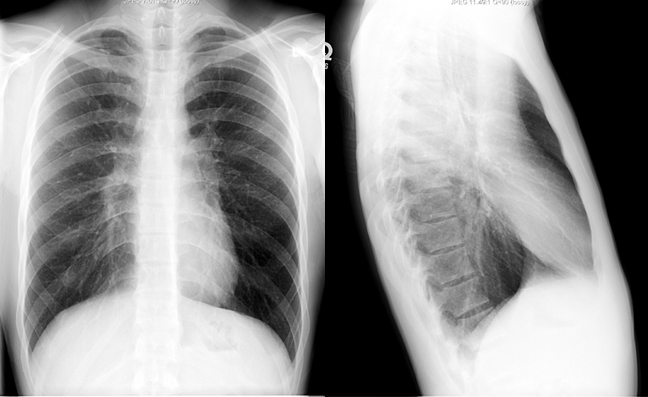

CXR of an asthmatic during an episode of bronchospasm. Lungs are hyperinflated due to air trappping. This normalizes once bronchospasm is controlled.